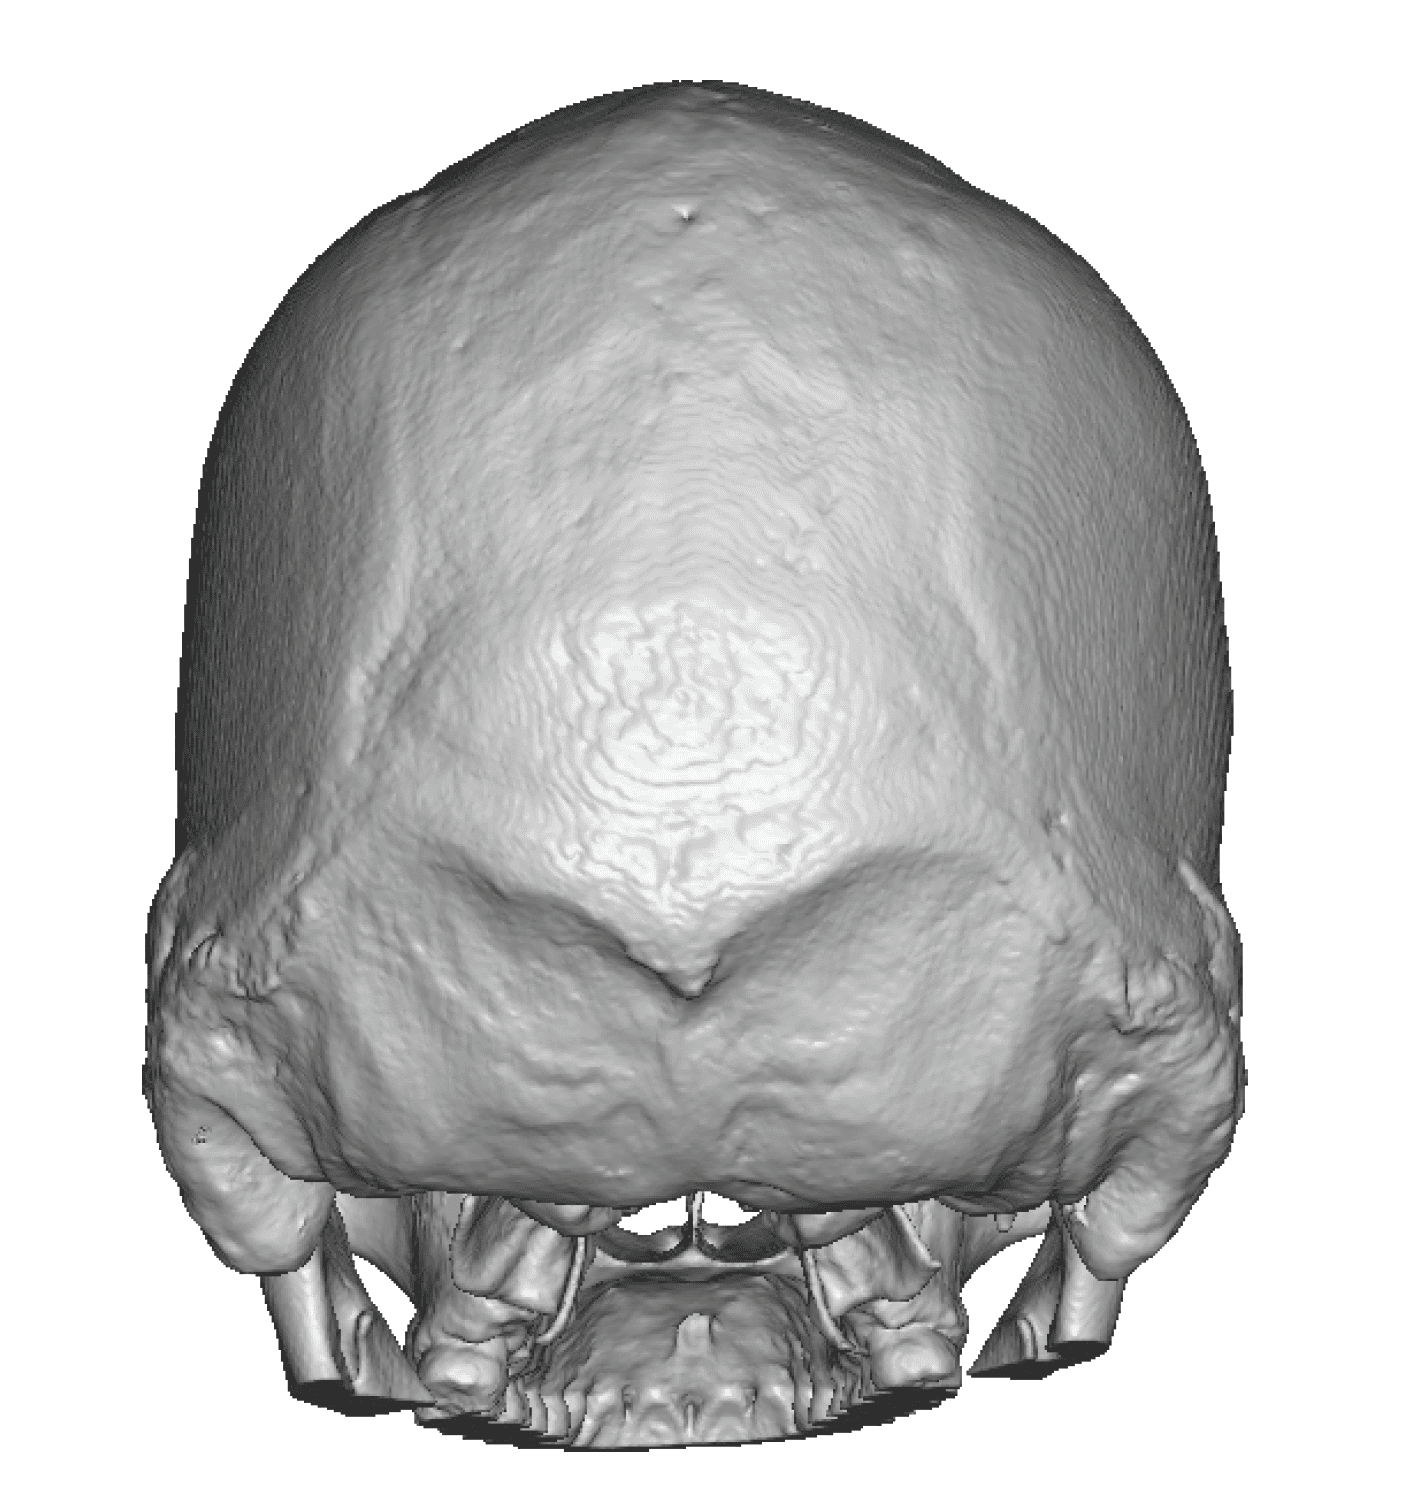

Severe narrowing skull deformity from prior sagittal craniosynostosis repair as an adult.

Complete replacement of entire skull by a custom implant with temporal fat injections.

Severe narrowing skull deformity from prior sagittal craniosynostosis repair as an adult.

Complete replacement of entire skull by a custom implant with temporal fat injections.